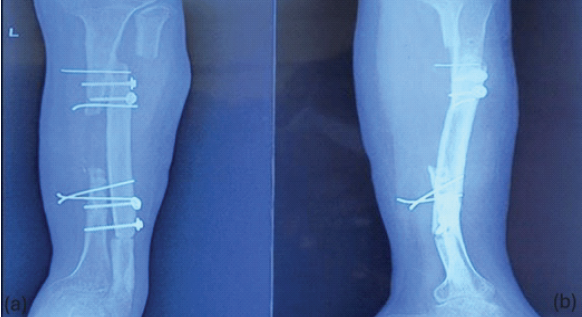

Follow-up X-rays were taken at 6 months (Fig. 6).

Figure 6: X-ray anteroposterior (a) and lateral (b) views after 6 months showing proximal tibio-fibular union (synostosis).

The functional outcomes achieved in this case further validate the efficacy of the modified technique. Radiological evidence of proximal tibiofibular union was observed within 3 months, and the patient demonstrated a painless range of motion in the knee (0–130°) and ankle dorsiflexion (15°) with normal plantar flexion (30°). Functional outcome scores could not be applied as the affected limb had pre-existing poliomyelitis. Due to limited resources, magnetic resonance angiography could not be done to objectively assess the graft viability and vascular continuity. The cosmetic outcome, marked by a healed surgical scar, was also satisfactory.